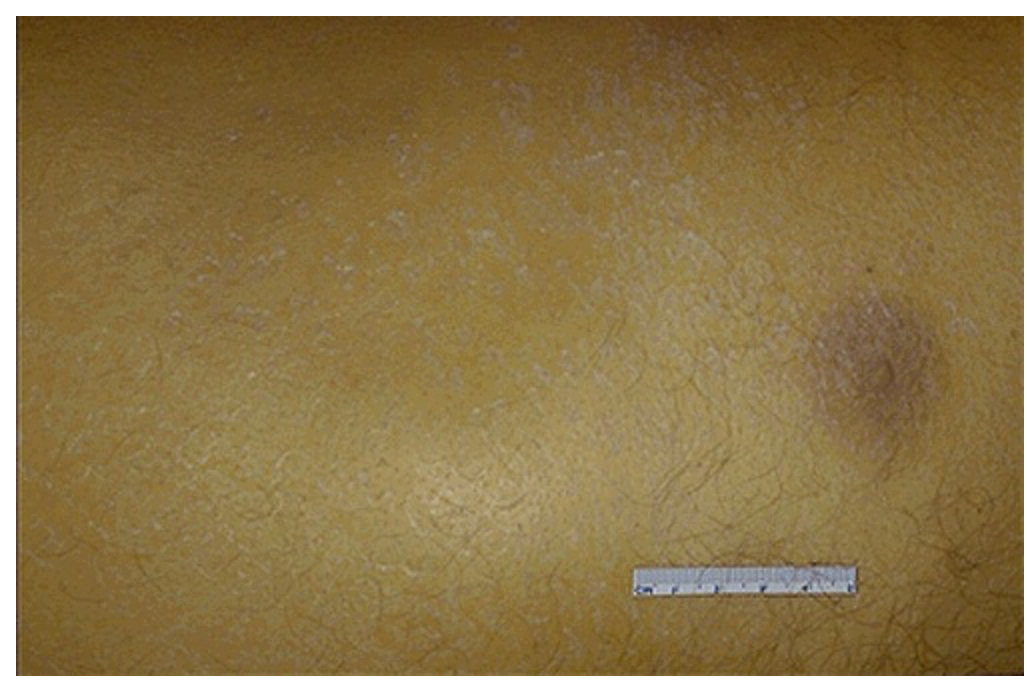

Gross anatomy of a Liver with Injury caused by chronic alcoholism. This leads to ______ and regeneration of the hepatocytes in nodules. The firm, nodular appearance of the liver is called ______

Fibrosis; Cirrhosis